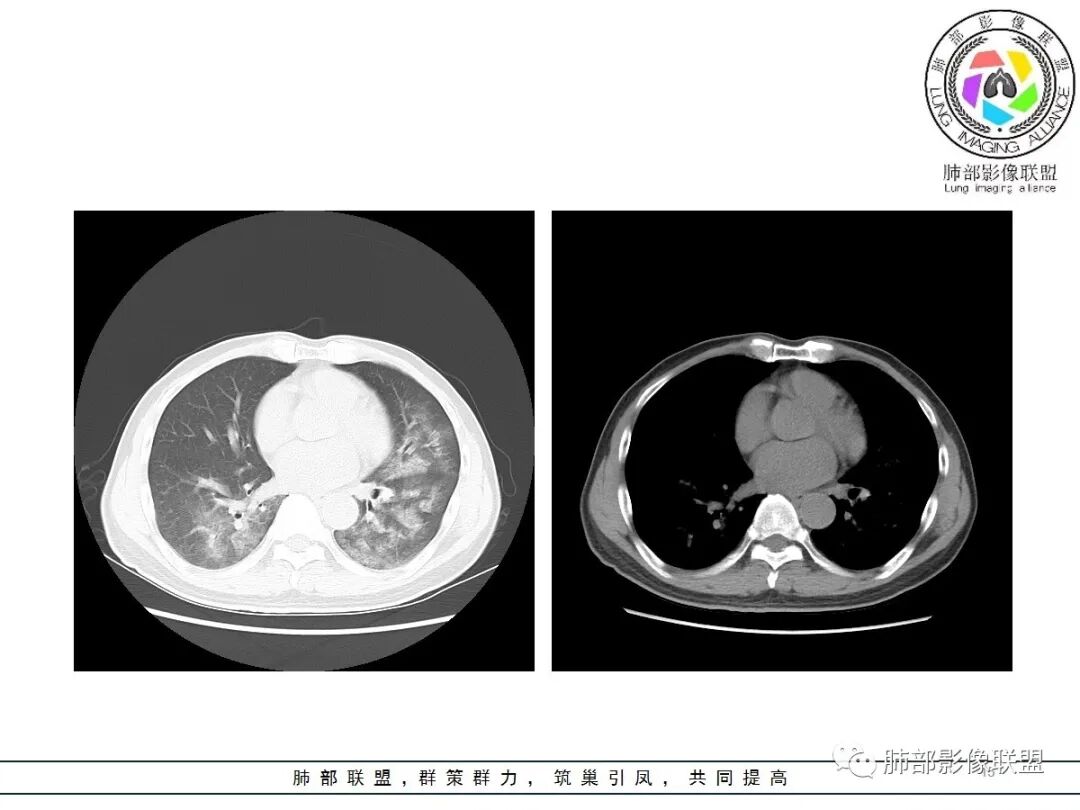

影像:双肺对称性中内带为主分布磨玻璃影,实变不明显。无胸水及小叶间隔增厚。

影像是符合肺水肿

已有临床资料可以排除心源性和肾源性水肿

(1)中央型分布:以肺门为中心,两肺中内带对称分布的大片状实变,称为“蝶翼征”。常见于心源性及肾源性肺水肿患者。也可表现为磨玻璃密度病灶,弥漫性分布或以小叶中心性分布。

(4)病变动态变化较快,在1~2d或数小时内可有显著变化。

神经源性肺水肿(neurogenic pulmonry edema,NPE)是指在无原发性心、肺和肾脏疾病情况下,由于颅脑损伤或中枢神经系统其他疾病引起突发性颅内压增高,从而导致急性肺水肿,又称脑源性肺水肿、中枢性肺水肿。其特点是起病急骤、进展快、治疗困难、病死率高(60%-100%)。